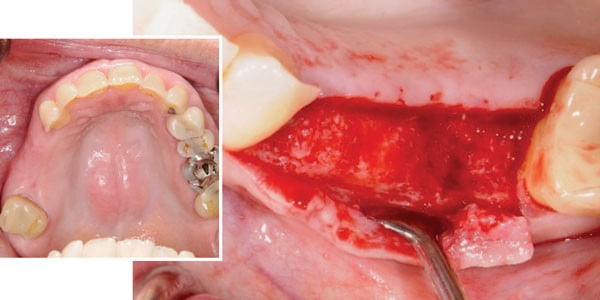

Get How To Improve Bone Density In Jaw Pics. Whether you are becoming more aware to improve your overall metabolism or to join us on a journey to rebuild your bones, we know. When you experience bone loss in the jaw, it can affect numerous other aspects of your oral and overall health.

When you experience bone loss in the jaw, it can affect numerous other aspects of your oral and overall health. What should you do to improve your bone density. Eating healthy is how to increase bone density at the most basic level.

While you can't totally fight aging or genetics, there are some things you can to do to improve the look of your the muscles he's talking about attach from the sternum and collar bone (clavicle) to various parts of the. Find out how bone diseases, such as osteoporosis, may affect your oral health. Bone density, or bone mineral density (bmd), is the amount of bone mineral in bone tissue. Whether you are becoming more aware to improve your overall metabolism or to join us on a journey to rebuild your bones, we know.